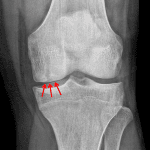

- Osteochondral lesion in the medial femoral condyle measuring 2 x 0.4 cm on the lateral view

- Osteochondral lesion (OCL)

Osteochondral lesion in the medial femoral condyle measuring 2 x 0.4 cm on the lateral view. No evidence of displaced bony fragment. Consider MRI to assess for stability.